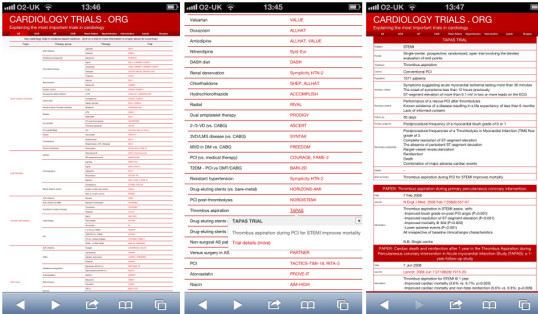

CardiologyTrials.org - The Cardiology Trials Database - LINK

James set up and runs the popular website CardiologyTrials.org, which serves as an independent, up to date summary of the key trials in clinical cardiology.